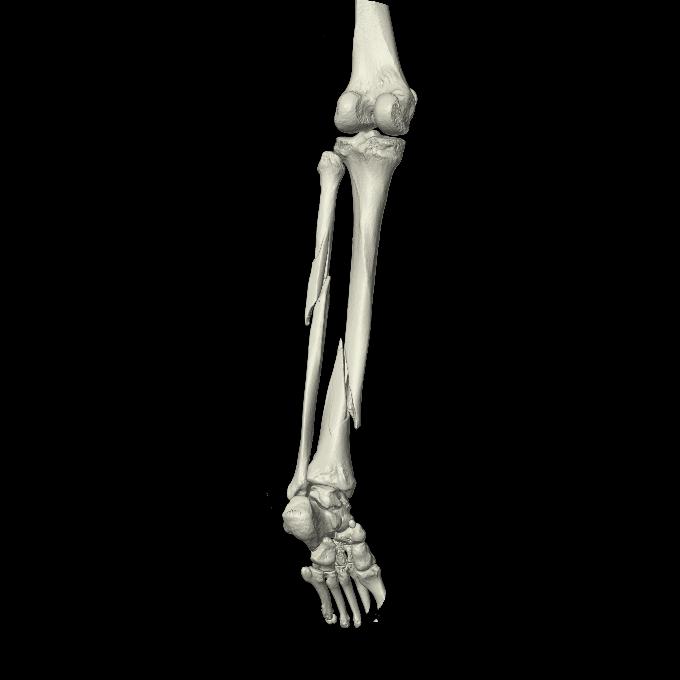

102803 1/12(キウスなし) 1/27 左下腿 4R 30歳女性 左脛骨軸内釘